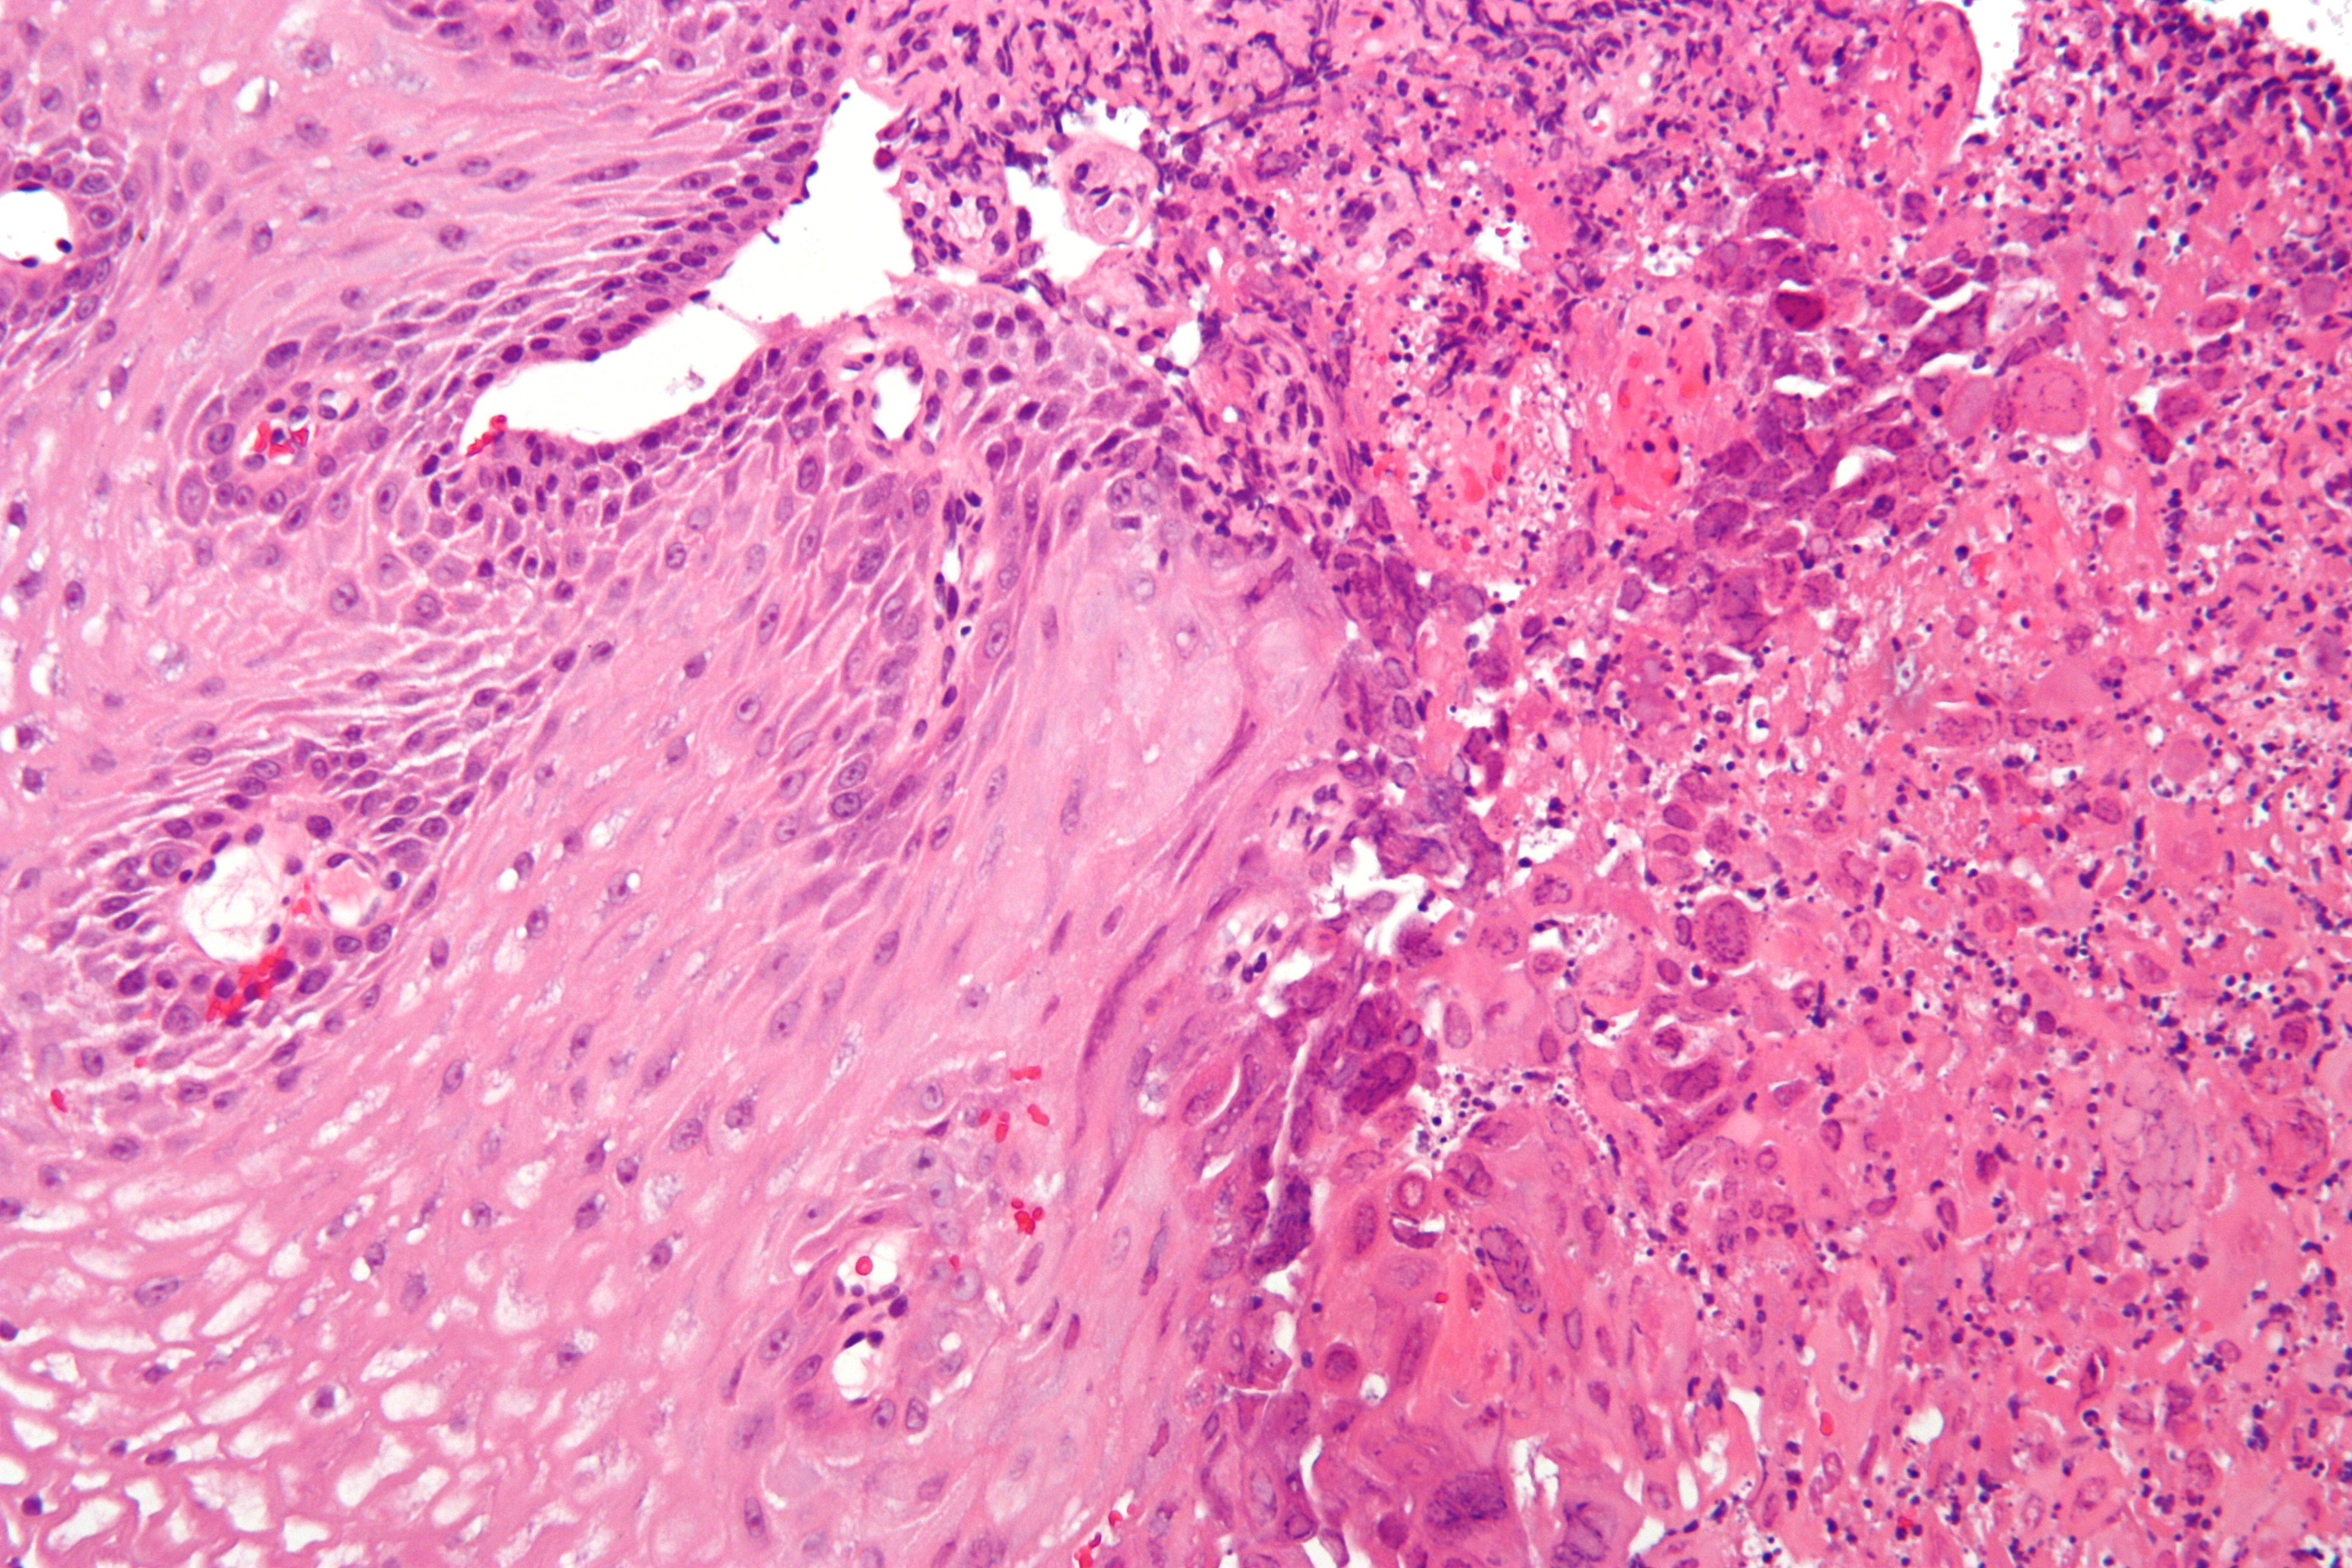

감염성 식도염은 바이러스, 곰팡이, 기생충 또는 세균 감염으로 인해 발생하며, 면역 결핍이 있는 사람에게 더 자주 발생한다. 감염성 식도염의 유형은 다음과 같다.- 곰팡이: 칸디다 (식도 칸디다증)

내시경을 통해 이러한 감염성 식도염들을 구별할 수 있다.[12]

식도염은 상부 내시경 검사, 생체 검사, 상부 위장관 조영술(또는 바륨 연하 검사) 및 실험실 검사를 통해 진단할 수 있다.[4]

상부 내시경 검사는 내시경을 사용하여 식도를 관찰하는 시술이다. 식도를 관찰하는 동안 의사는 작은 생체 검사를 채취할 수 있다. 생체 검사는 식도 염증을 확인하는 데 사용될 수 있다.

식도에서 채취한 생체 검사에서 실험실 검사를 수행하여 식도염의 원인을 파악하는 데 도움을 줄 수 있다. 실험실 검사는 곰팡이, 바이러스 또는 세균 감염을 진단하는 데 도움이 될 수 있다. 백혈구 검사는 호산구 식도염을 진단하는 데 도움이 될 수 있다.